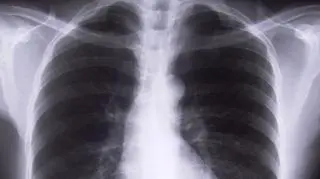

Jutro światowy dzień POChP, czyli przewlekłej obturacyjnej choroby płuc. W studiu Dzień Dobry TVN gościem był dr Piotr Dąbrowiecki, lekarz alergolog. To choroba, której objawy przebiegają niezauważalnie. Jej główną przyczyną jest palenie tytoniu. Dlaczego coraz częściej chorują na nią kobiety? Jak bardzo groźna jest to choroba i jakie są skutki jej nieleczenia?